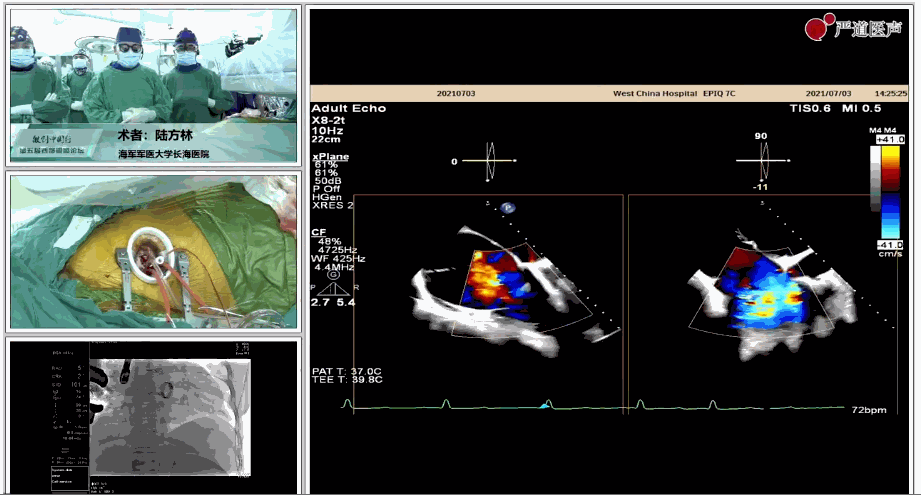

陸方林教授分享的是一例極重度三尖瓣返流的患者采用健世科技(LuX-Valve®)經(jīng)導(dǎo)管三尖瓣置換系統(tǒng)進(jìn)行的手術(shù)直播演示。此例患者為69歲女性,入院前17年行二尖瓣機(jī)械瓣置換術(shù),術(shù)后長期服用華法林抗凝,既往“2型糖尿病”病史5年,“雙下肢水腫”3年。3個(gè)月前患者出現(xiàn)腹脹、雙下肢水腫,伴活動(dòng)后暈厥,伴黃疽、皮膚濕癢、牙齦出血,癥狀持續(xù)加重,遂入院治療。入院后行心臟CT、心臟超聲檢查,提示:“三尖瓣關(guān)閉不全(極重度),二尖瓣置換術(shù)后,心功能III級”。徐志云、陸方林微創(chuàng)三尖瓣置換團(tuán)隊(duì)對該患者的病情進(jìn)行了充分的評估和討論。由于患者有開胸二尖瓣置換手術(shù)史,且病史時(shí)間長,同時(shí)存在相關(guān)合并癥,傳統(tǒng)外科手術(shù)風(fēng)險(xiǎn)極高(STS評分:8.315%),最終決定采用三尖瓣LuX-Valve®瓣膜系統(tǒng)對患者進(jìn)行治療。

▲術(shù)中食道超聲顯示三尖瓣極重度返流

▲瓣膜植入后三維超聲影像

▲瓣膜植入后右心室造影

在手術(shù)直播中瓣膜植入過程不到10分鐘,手術(shù)獲得圓滿成功,充分體現(xiàn)徐志云、陸方林團(tuán)隊(duì)技術(shù)精湛,團(tuán)隊(duì)協(xié)作默契及器械的優(yōu)越性。

該例患者返回后當(dāng)天拔除氣管插管,生命體征穩(wěn)定,恢復(fù)良好。此次會(huì)議不僅有最前沿的學(xué)術(shù)講座,更有3D體驗(yàn)般的手術(shù)直播,為大家第一視角直觀呈現(xiàn)領(lǐng)域新技術(shù)、新策略、新思路。